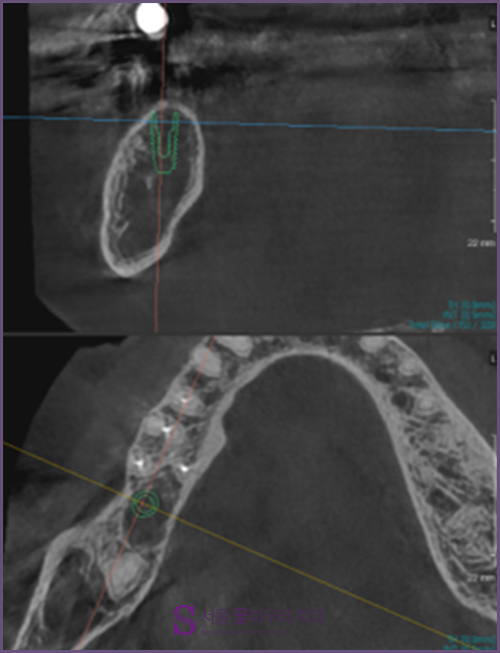

내과와 협의한 후 기존 약을 5일 정도 복용을 중단하고 임플란트 2개를 심기로 결정했습니다 이 사진은 환자분의 3DCT사진입니다. 상하 임플란트 매립을 희망하셨기 때문에 픽스처가 매입할 뼈의 길이와 골질이 충분히 확보되어 있는지 확인했습니다. 위턱은 문제가 없었지만 아래턱 부분에 골밀도가 부족했기 때문에 2회로 나누어 치료를 하게 되었습니다.

아래 사진을 보시면 초록~파랑으로 나타나는 부분은 임플란트를 박기에 골밀도가 충분하고, 붉게 나타나는 부분은 골밀도가 부족한 부분입니다. 한 눈에 봐도 푸르스름한 부분보다는 붉은 부분이 많다는 것을 알 수 있습니다. 따라서 위턱은 1차와 2차 시술을 동시에 진행하였으나 아래턱은 충분한 회복기간을 두고 시술하여 환자들이 만족할 수 있는 대구 임플란트를 완료하였습니다.